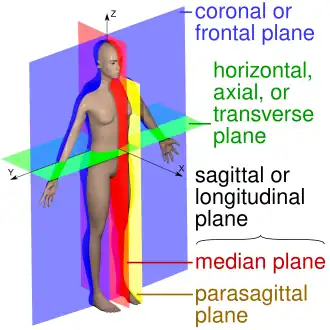

Human anatomy planes, with median plane in red. | |

Whether in reference to the anatomy of the human or other members of the Bilateria, the median plane, also called the midsagittal plane and related terms, is used to describe the sagittal plane as it bisects the body vertically through the midline marked by the navel, dividing the body exactly in left and right side. The term parasagittal plane is used to refer to any plane parallel to the sagittal and median plane.[1][2][3]